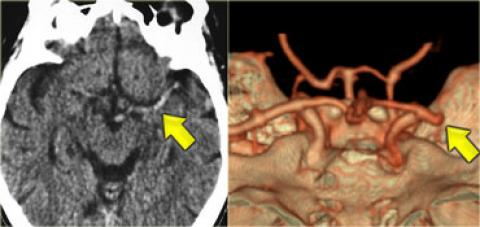

Hình ảnh tăng tỷ trọng động mạch não giữa MCA bên trái, do huyết khối hoặc tắc mạch. Tương ứng với tắc MCA trên CTA.

Hình ảnh tắc động mạch não giữa MCA bên phải trên CTA